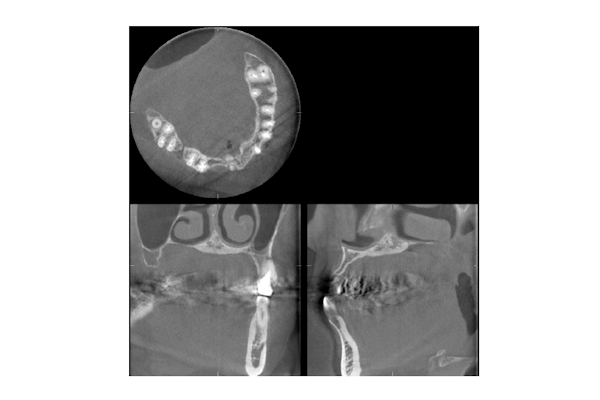

1枚目の写真は、抜歯後インプラントを入れるため骨造成をすることになり、人工骨を入れ8ヶ月待ったのですが十分な骨が出来ずその歯科医院を不審に思い来院されました。